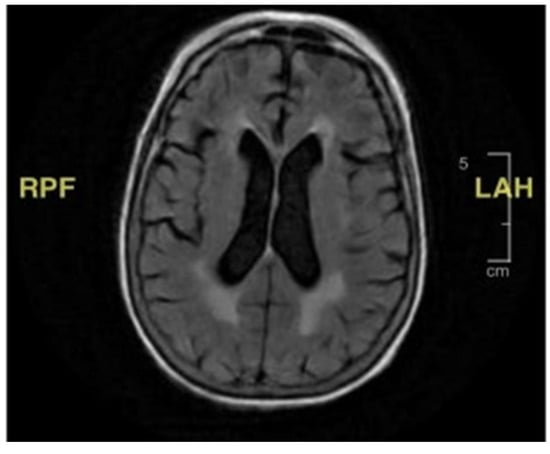

Figure 1. Brain magnetic resonance imaging (MRI). There is no mass effect, hemorrhage, edema, midline shift, or extra cerebral fluid collection. The ventricles and subarachnoid spaces are appropriate in size for the patient’s age.